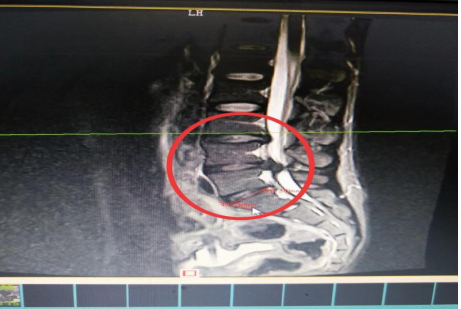

10分鐘后,患者肖先生沒有家屬陪同的情況下被緊急到骨科一區(qū)病房。接診滿頭大汗、非常緊張肖先生,舒小林醫(yī)師仔細(xì)詢問(wèn)了病情原來(lái)肖先生從事搬運(yùn)行業(yè),半年前就腰腿痛就醫(yī),當(dāng)時(shí)在保守治療后稍有緩解,沒有引起重視。直到11月13日下午因搬重物后突然感到腰腿劇烈疼痛、麻木、大小便困難,這才120急救電話。骨科一區(qū)錢軍副主任、舒小林醫(yī)師立即給患者作了詳細(xì)的體查,并立即聯(lián)系做急診腰椎磁共振確定有無(wú)神經(jīng)受壓。腰椎磁共振結(jié)果提示:腰4/腰5椎間盤膨出,導(dǎo)致馬尾神經(jīng)嚴(yán)重受壓,有明顯的手術(shù)指征,如不盡快手術(shù)會(huì)致神經(jīng)受損難以恢復(fù)。錢軍副主任來(lái)到肖先生病床前,將手術(shù)方案、手術(shù)風(fēng)險(xiǎn)及并發(fā)癥詳細(xì)告知肖先生本人,肖先生表示同意并簽字馬上手術(shù)。